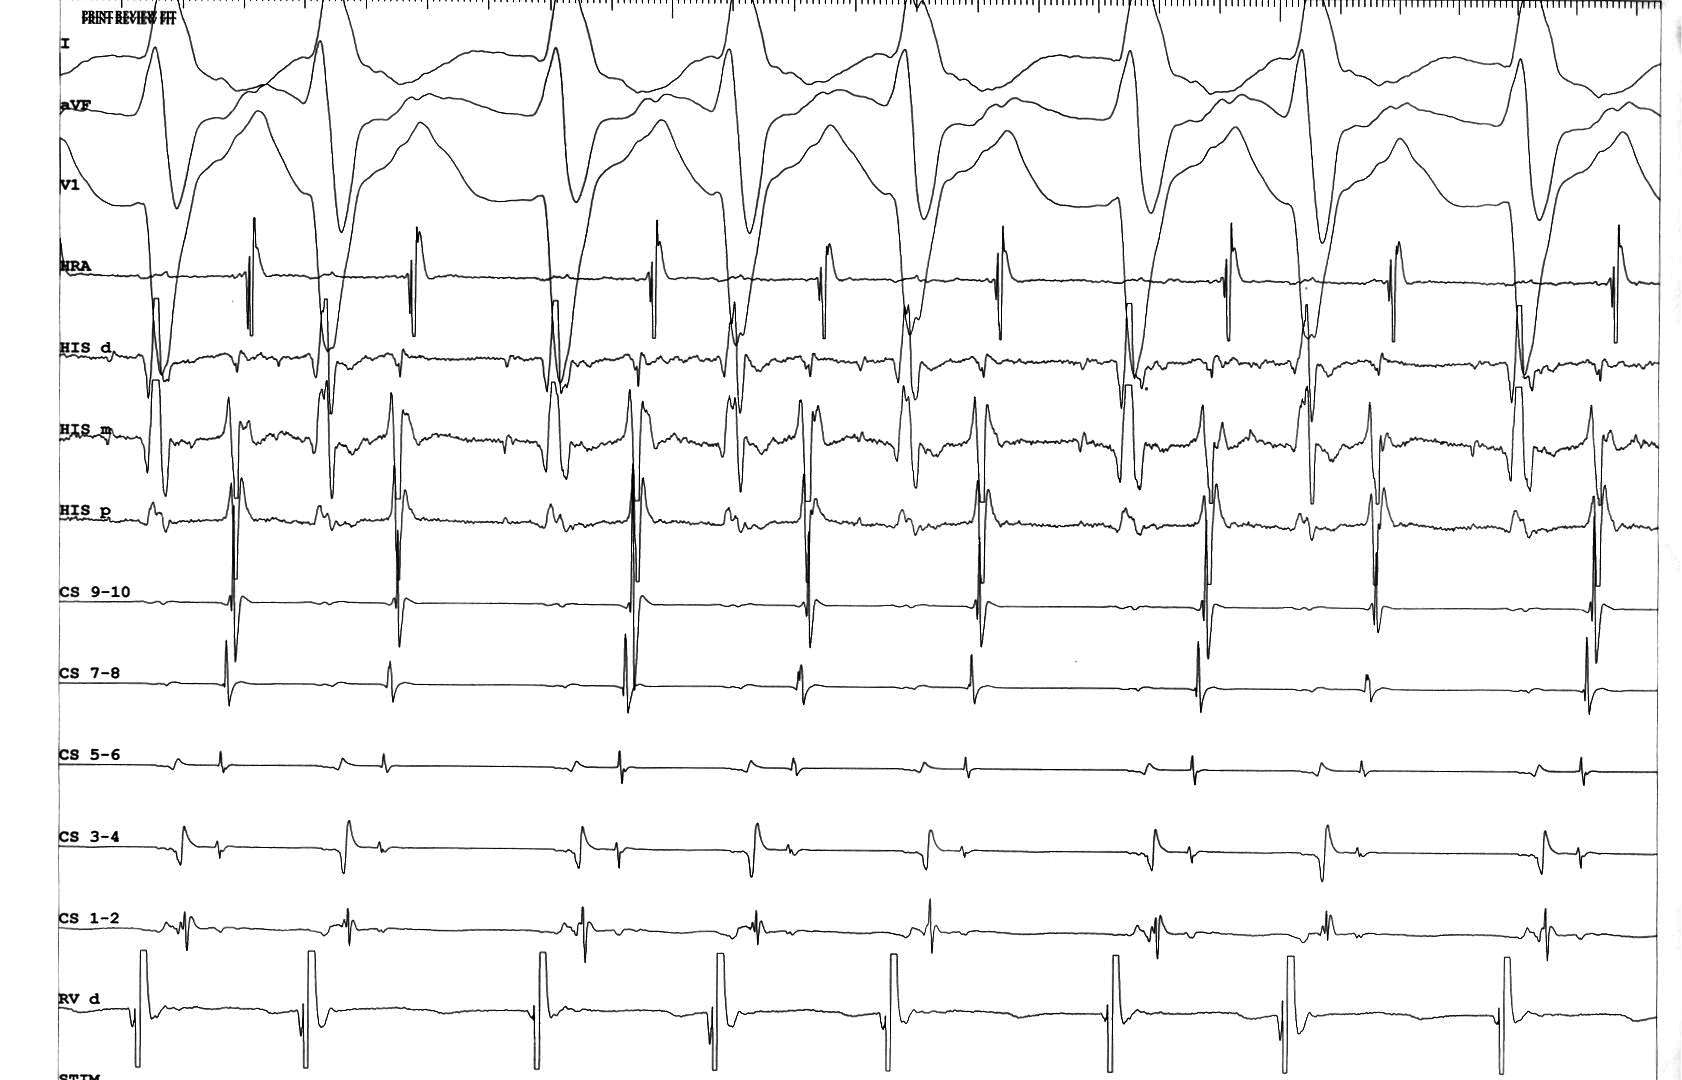

Middle of VOP

02_constant and progressive fusion.JPG

Entrainment with antegrade His

entrain_with_fusion.jpg

Termination during VOP

termination_with_fusion.JPG